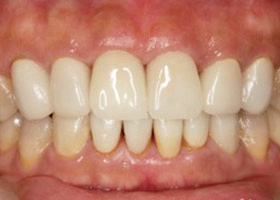

5. 矯正後,上顎外暴及下顎參差不齊的情況大幅改善。

6. 將假牙拆除後,重新取模。